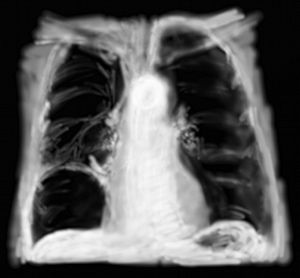

RP hernie hiatale

La hernie hiatale, béance de l’orifice diaphragmatique laissant passer l’oesophage thoracique dans l’estomac abdominal, est parfois très volumineuse et quand elle se produit par glissement, le haut de l’estomac peut saillir dans le thorax. Radiologiquement, une énorme bulle en projection du coeur apparait, l’aspect pourrait ressembler au précédent, mais si on arrive à suivre le trajet de la hernie on repère que c’est un processus venant de l’abdomen.

Pas forcément symptômatique, c’est souvent une découverte fortuite chez des patients très âgés.

La hernie hiatale par roulement est plus problématique puisque c’est la poche à air gastrique qui est herniée alors qu’une partie de l’oesophage reste intra-abdominale. C’est une éventualité assez rare quand même.